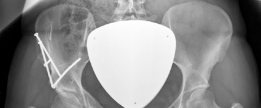

With the acetabular fragment now mobile, a 5.0mm Schanz pin is placed into the supra-acetabular region to act as a joystick. The fragment is mobilized and rotated laterally and anteriorly to achieve the pre-planned coverage. We also intentionally medialize the fragment to optimize the abductor lever arm. The hip is taken through a full range of motion to ensure there is no iatrogenic anterior impingement. Fluoroscopy is utilized extensively at this stage. We obtain AP, false profile, and obturator oblique views to confirm the correction of the LCEA, ACEA, and Shenton's line, and to ensure the joint space remains perfectly congruent.

Once the optimal position is achieved and verified, provisional fixation is obtained with Kirschner wires. Definitive fixation is then achieved using three or four fully threaded 4.5mm cortical screws directed from the intact ilium down into the acetabular fragment. The screws must be carefully placed to avoid intra-articular penetration. After final fluoroscopic confirmation, the rectus femoris is reattached to the AIIS, and the wound is closed in layers over a deep subfascial drain. The skin is closed with a subcuticular suture to optimize the cosmetic outcome for this young patient.